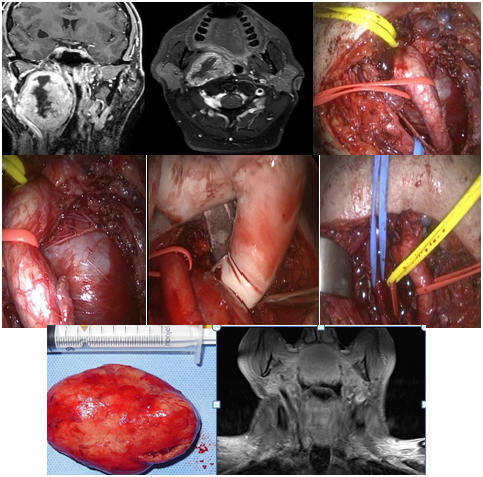

The function of the facial nerve was completely preserved in 2 patients (Brackmann I), another one had a slight dysfunction in the mandibular branch (Brackmann II: minimal asymmetry of movement in the mouth) and in another, nerve function was more affected (Brackmann III). The average period of control in this group was 4 years, and no recurrence was detected in the MRI (Figure 1–3).

Figure 1 Neurilemoma of the facial nerve at the parotid gland. Mastoidectomy, parotidotomy and intracapsular tumor resection

Figure 2 Schwannoma of the facial nerve at the parotid gland. Intracapsular resection with preservation of nerve function.

In three patients, a facial nerve monitor was used, and the incision was made in order to make the subcapsular dissection in an area that did not generate stimulation; in one, a mastoidectomy was performed to achieve a better expose of main facial nerve trunk, combined with the parotidotomy.